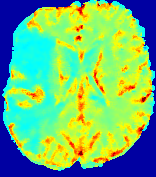

LesionRefer to captionRefer to captionRefer to captionRefer to captionRefer to captionRefer to caption𝐕rgbsubscript𝐕𝑟𝑔𝑏{\bf{V}}_{rgb}Refer to captionRefer to captionRefer to captionRefer to captionRefer to captionRefer to caption𝐕2subscriptnorm𝐕2{\|\bf{V}}\|_{2}Refer to captionRefer to captionRefer to captionRefer to captionRefer to captionRefer to captionRefer to caption3.53.53.52.82.82.82.12.12.11.41.41.40.70.70.70.00.00.0(mm/s)𝑚𝑚𝑠(mm/s)D𝐷DRefer to captionRefer to captionRefer to captionRefer to captionRefer to captionRefer to captionRefer to caption0.0200.0200.0200.0160.0160.0160.0120.0120.0120.0080.0080.0080.0040.0040.0040.0000.0000.000(mm2/s)𝑚superscript𝑚2𝑠(mm^{2}/s)Slice #1Slice #2Slice #3Slice #4Slice #5Slice #6

Figure 3: PIANO feature maps for one stroke patient, where the lesion is located in the left hemisphere. Top row: segmented stroke lesion region (white) on different slices, obtained from ISLES 2017. The corresponding slices for the PIANO feature maps are shown in the following rows.

For a better insight into an estimated velocity field 𝐕𝐕{\bf{V}} and diffusion field 𝐃𝐃{\bf{D}}, we compute the following maps: (1) 𝐕rgbsubscript𝐕𝑟𝑔𝑏{\bf{V}}_{rgb}: Color-coded orientation map of 𝐕=(Vx,Vy,Vz)T𝐕superscriptsuperscript𝑉𝑥superscript𝑉𝑦superscript𝑉𝑧𝑇{\bf{V}}=(V^{x},V^{y},V^{z})^{T}, obtained by normalizing 𝐕𝐕{\bf{V}} to unit length and mapping its 3 components to red, green, blue respectively; (2) 𝐕2subscriptnorm𝐕2\|{\bf{V}}\|_{2}: 222 norm of 𝐕𝐕{\bf{V}}; (3) D𝐷D: scalar field in Eq. 5.

Fig. 3 and Fig. 4 show the PIANO feature maps estimated from two ISLES 2017 patients: all are highly consistent with the lesion in both cases. Details of the blood flow trajectories are revealed in 𝐕rgbsubscript𝐕𝑟𝑔𝑏{\bf{V}}_{rgb} by the ridged patterns and the sharp changes of colors in the unaffected (right) hemisphere, while the flat patterns appearing within the lesion provide little directional information about the velocity and indicate low velocity magnitudes. Velocity magnitudes are more directly visualized via 𝐕2subscriptnorm𝐕2\|{\bf{V}}\|_{2}, from which one can easily locate the lesion where 𝐕2subscriptnorm𝐕2\|{\bf{V}}\|_{2} is low. D𝐷D also indicates lower diffusion values in the lesion, though with less contrast potentially due to the fact that it captures the accumulated effect of CA diffusion at the voxel-level.